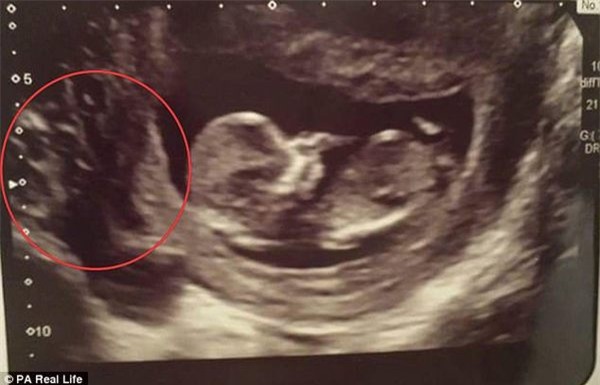

"Khi quay màn hình về phía chúng tôi, tôi nhìn thấy rất nhiều hố đen, ở nơi mà đáng ra em bé phải đang hình thành với kích thước một quả nho."

"Tôi thậm chí còn không thể nhìn thấy phần lớn bào thai, và bác sĩ nói rằng có thể tôi đang gặp phải tình trạng mang thai trứng. Tôi chưa từng nghe về nó, nhưng cô ấy giải thích tình trạng này diễn ra khi một khối u bất thường hình thành trong tử cung, thay vì một bào thai khỏe mạnh, và trong những trường hợp đặc biệt, nó có thể là khối ung thư".

Khi đến gặp chuyên gia về lĩnh vực này, bác sĩ một lần nữa khẳng định rằng mang thai trứng một phần gần như là lí do chắc chắn nhất có thể lí giải được về những lỗ đen lớn tại phần nhau thai nhìn như các lỗ trên tổ ong đang phát triển bên cạnh em bé của Mickayla.

Tuy nhiên, khi theo dõi sát sao tình trạng thai nhi, Mickayla và chồng mình, cũng như đội ngũ bác sĩ đều rất ngạc nhiên khi nhìn vào màn hình siêu âm hàng tuần, thấy những lỗ đen cứ lớn dần lên bên cạnh em bé. Điều kì lạ là, em bé dường như chẳng hề hấn gì từ "sự uy hiếp" của những lỗ đen cứ lớn dần lên.

Vào buổi siêu âm tuần thứ 26, hai vợ chồng vẫn chưa thể nhìn thấy được em bé do bị che lấp bởi những lỗ đen lớn.